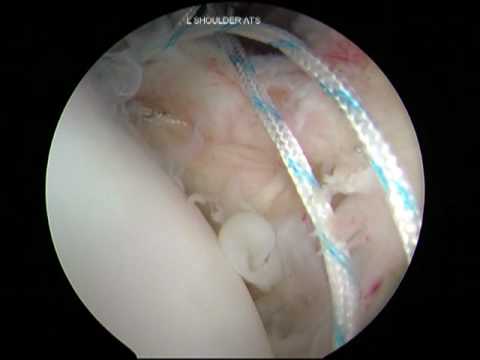

Arthroscopic Posterior HAGL Repair and Reconstruction

Cascio Shoulder Instability Arthroscopy: HAGL Lesion Part 3 of 3